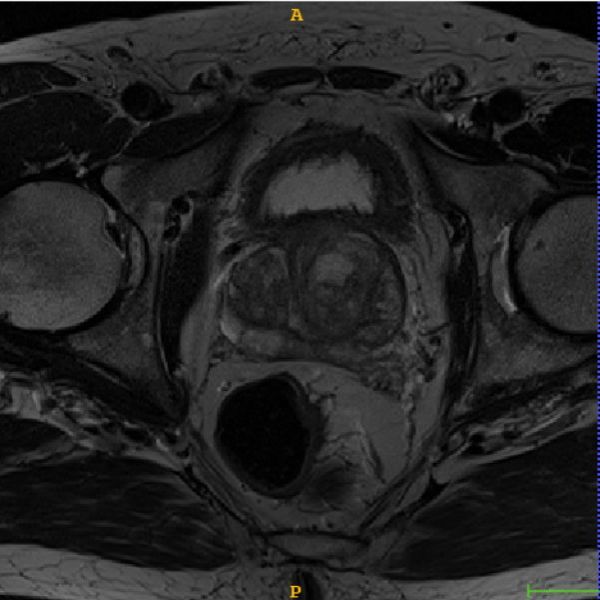

2 Backends

M3d-CAM supports multiple methods for generating the attention maps. For simplicity we will refer to them as backends. For a better understanding of how these attention maps look like we included examples for every backend. The original input images are shown in figure 3. The first image displays a chest X-Ray used on the task of classification by employing a CovidNet [2], the second a lung CT slice on the task of 2D segmentation by employing an Inf-Net [3] and the third a 3D prostate CT image on the task of 3D segmentation by employing a nnUNet [4].

Refer to caption

Figure 3: From left to right: A chest X-Ray from the COVID-19 image data collection [5], a lung CT slice also from [5] and 3D prostate CT image from the Medical Decathlon dataset [6]